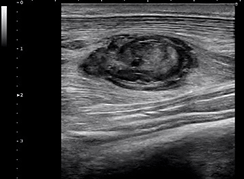

前腕筋損傷筋内血腫

超広帯域プローブとこの帯域を最大限利用するためのTriad-THI技術により、体の表層や浅い部位のみならず、診断したい領域全域の高画質化が可能になり、診断精度向上に貢献できると考えています。